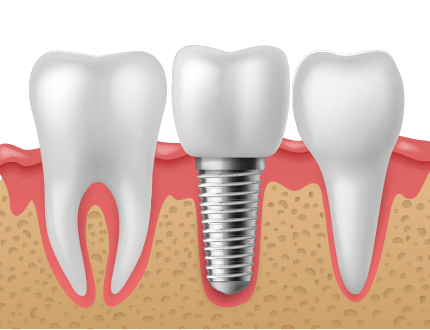

잇몸과 잇몸뼈 상태가 양호하게 잘 보존되어 있는 경우에는 치아를 발치하고 곧바로 임플란트를 식립할 수 있습니다.

그렇기 때문에 이러한 발치즉시 임플란트는 수술횟수와 치료기간을 줄일 수 있을 뿐만 아니라

잇몸조직의 손상이 적어서 회복이 빠른 장점이 있습니다.